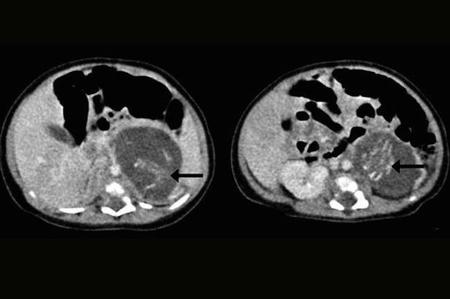

Arriba se puede ver la imagen de una tomografía computarizada de la niña en la que se ve la columna vertebral de los fetos y que ha quedado registrada, por su carácter extraordinario, en el último número de la revista Hong Kong Medical Journal.

Es sumamente raro que ocurra, pero en la mayoría de los casos se diagnostica en los primeros años de vida (un 89% antes de los 18 meses). A veces se puede detectar mediante ecografías en el embarazo, pero es complicado por lo pequeños que pueden llegar a ser los restos. En este caso, uno de los fetos pesaba 14,2 gramos y el otro 9,3 gramos.